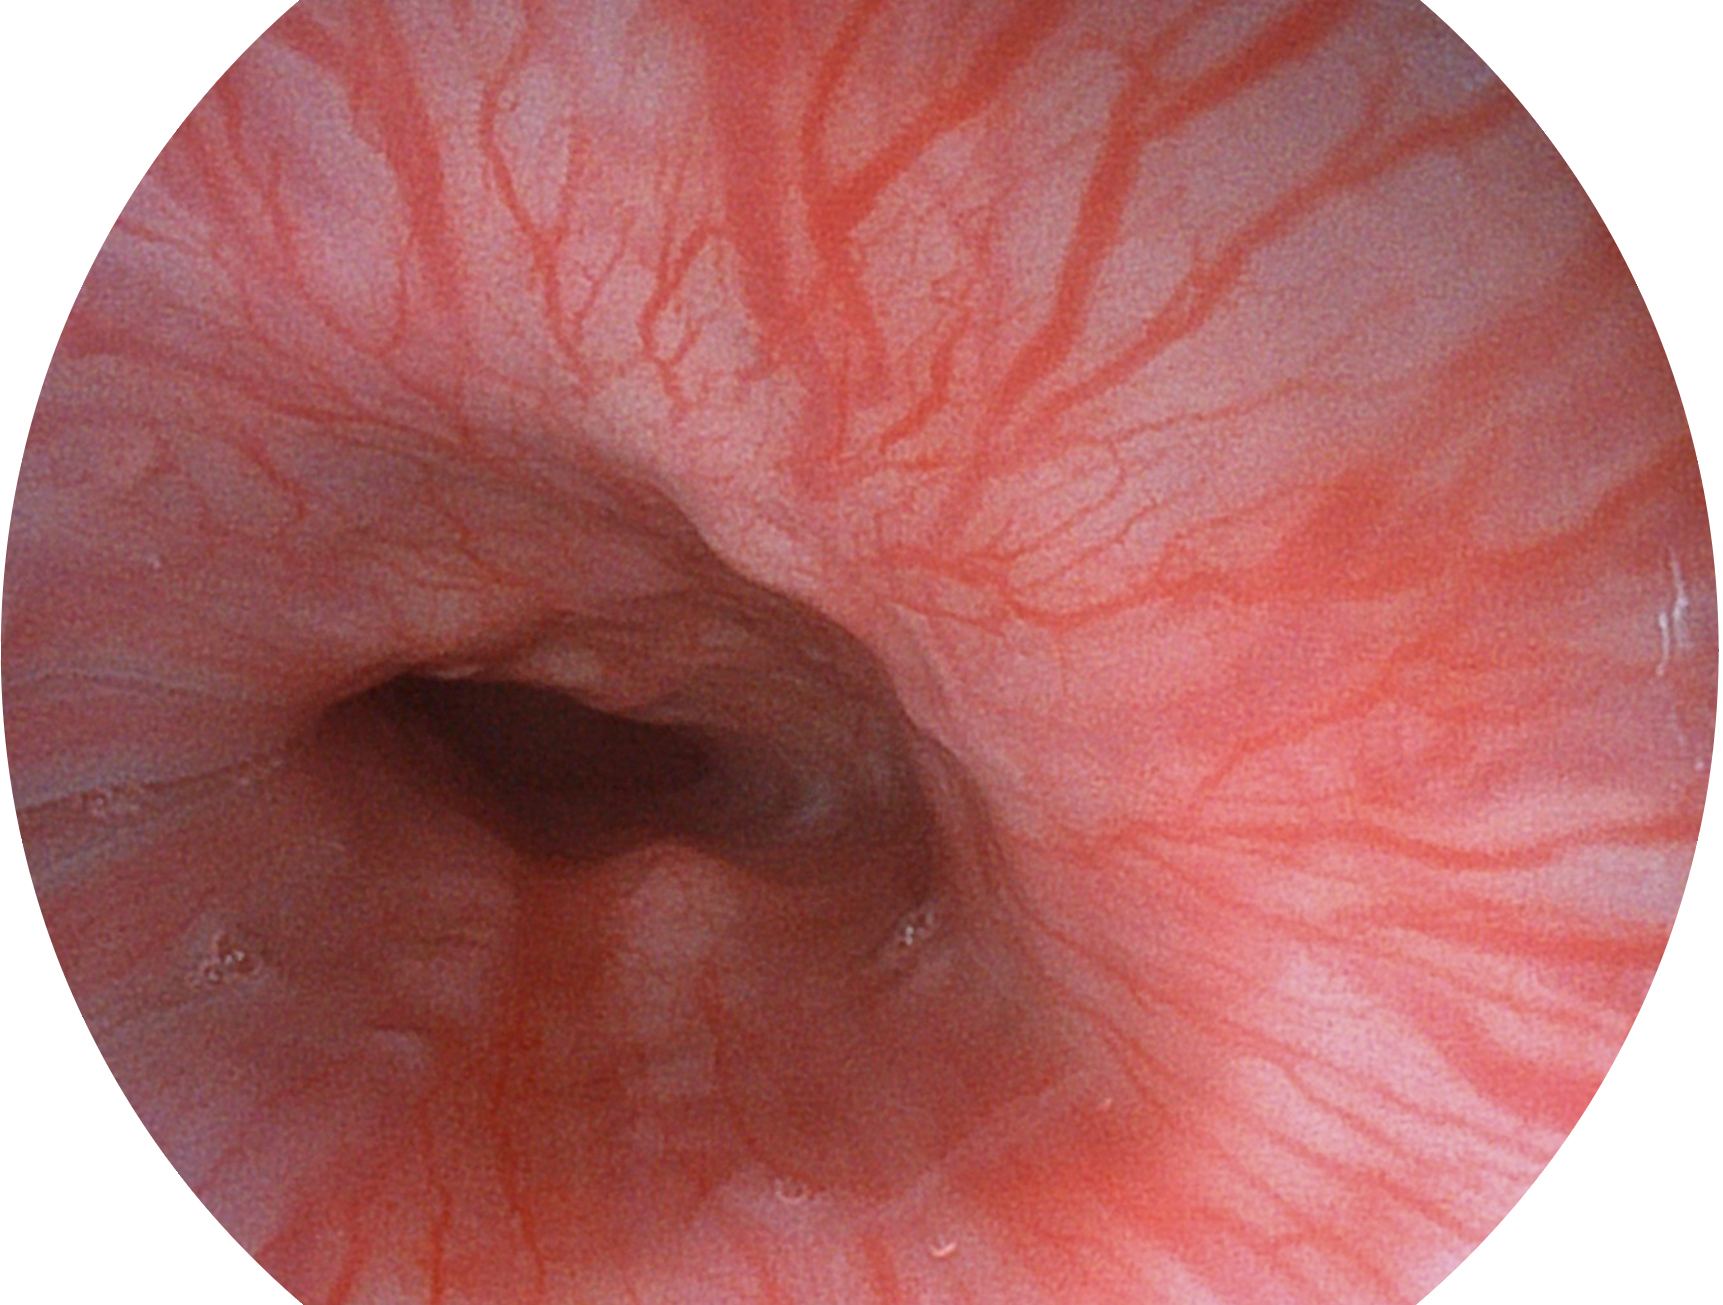

环球UG官网新开发的内镜染色技术,主要是基于多波长LED 光源的开发,VLS-55Q 四波长LED 光源是由四个不同颜色的LED光按照相应照明模式所规定的特定发光比例进行合束后形成,合束后形成的照明光的光谱由红光、绿光、蓝光及蓝紫光这四个不同的波段范围构成。具有更高光谱自由度,通过光谱比例的控制,实现了聚谱成像技术,英文全称为“Spectral Focused Imaging, SFI”,缩写为“SFI”和光电复合染色成像技术,英文全称为“Versatile Intelligent Staining Technology, VIST”,缩写为“VIST”。